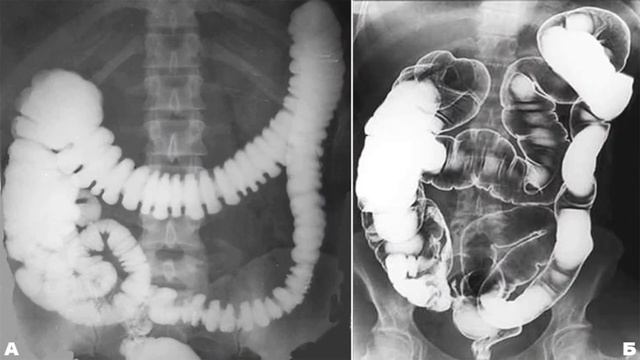

Рентгеноконтрастные Исследования Кишечника: Визуализация и Методики

Раздел: Иллюстрированный журнал